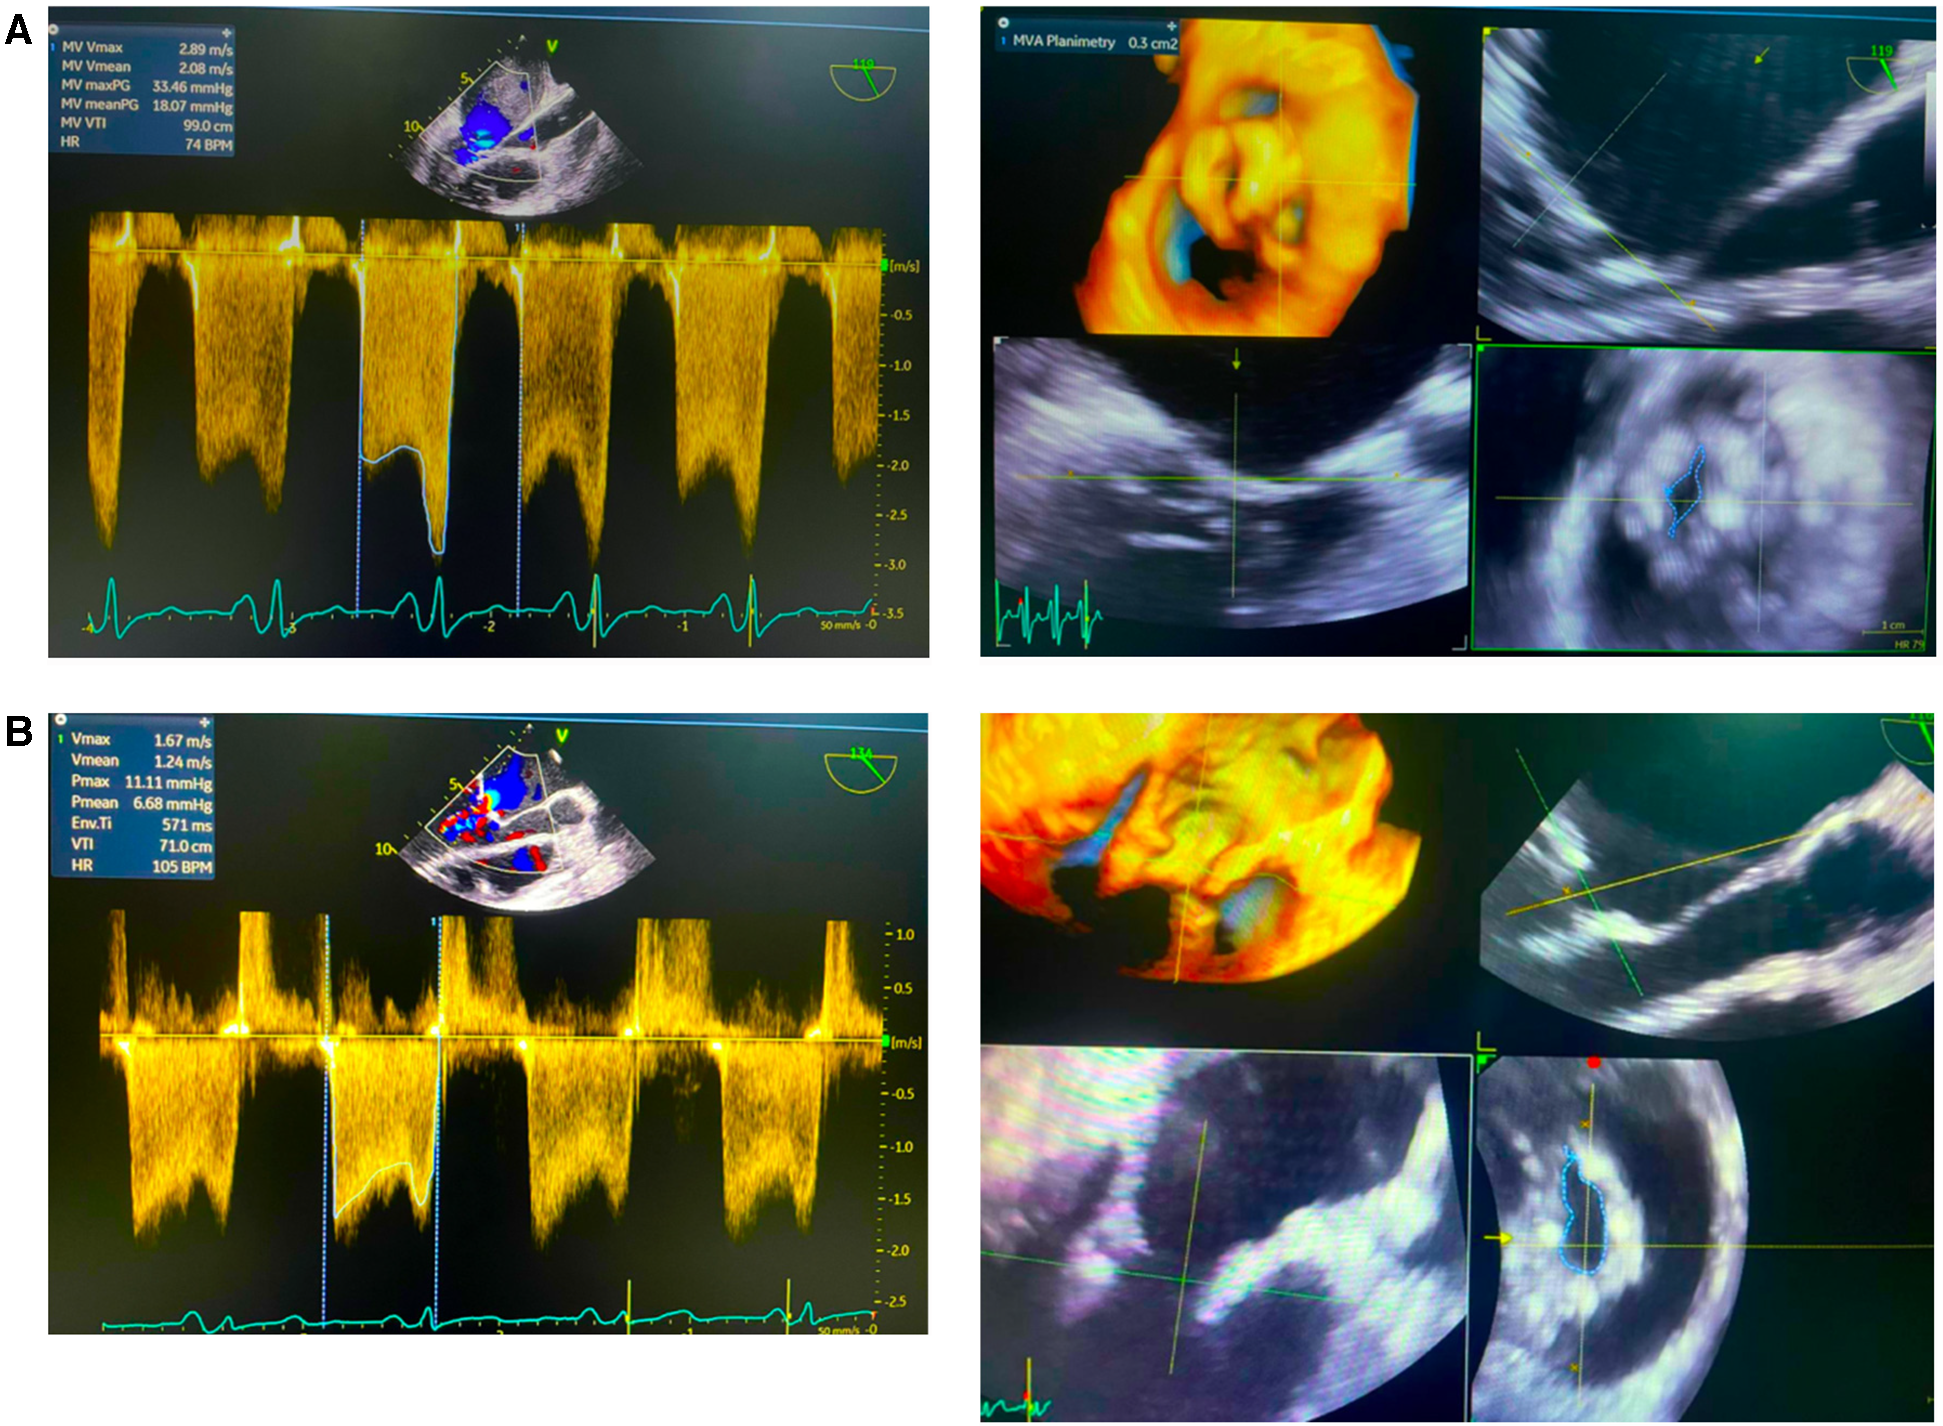

The procedure was successfully completed, as the MV area increased to 1 cm2, and the mean mitral valve gradient was reduced from 11 to 5 mmHg with no mitral regurgitation or hemodynamic disturbances observed (Figure 2). No complications occurred during or after the procedure. The patient was discharged in a stable state, and on follow-up, she has improved exercise tolerance.

Figure 2

Echocardiography pre- and post- percutaneous balloon mitral valvotomy (PBMV). (A) Initial data showed mean valve area (MVA) plannimetry was 0.3 cm and mean valve gradient (MVG) 18.7 mmHg. (B) Post PBMV showed mean valve area (MVA) plannimetry was 1.0 cm and mean valve gradient (MVG) 6.68 mmHg.